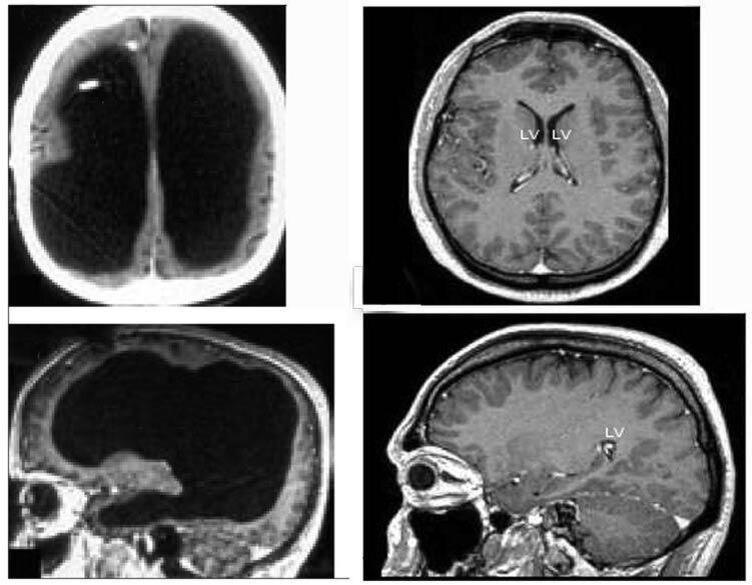

Результаты его МРТ озадачили всё медицинское сообщество. Выяснилось, что его череп на 90% заполнен жидкостью. У него сохранился только тонкий внешний слой мозгового вещества, а внутренняя часть мозга полностью отсутствовала.

Фото слева: мозг француза. Фото справа - мозг обычного человека.

Получается, что, если бы не нога, то этот человек жил бы и дальше, не подозревая о такой проблеме.